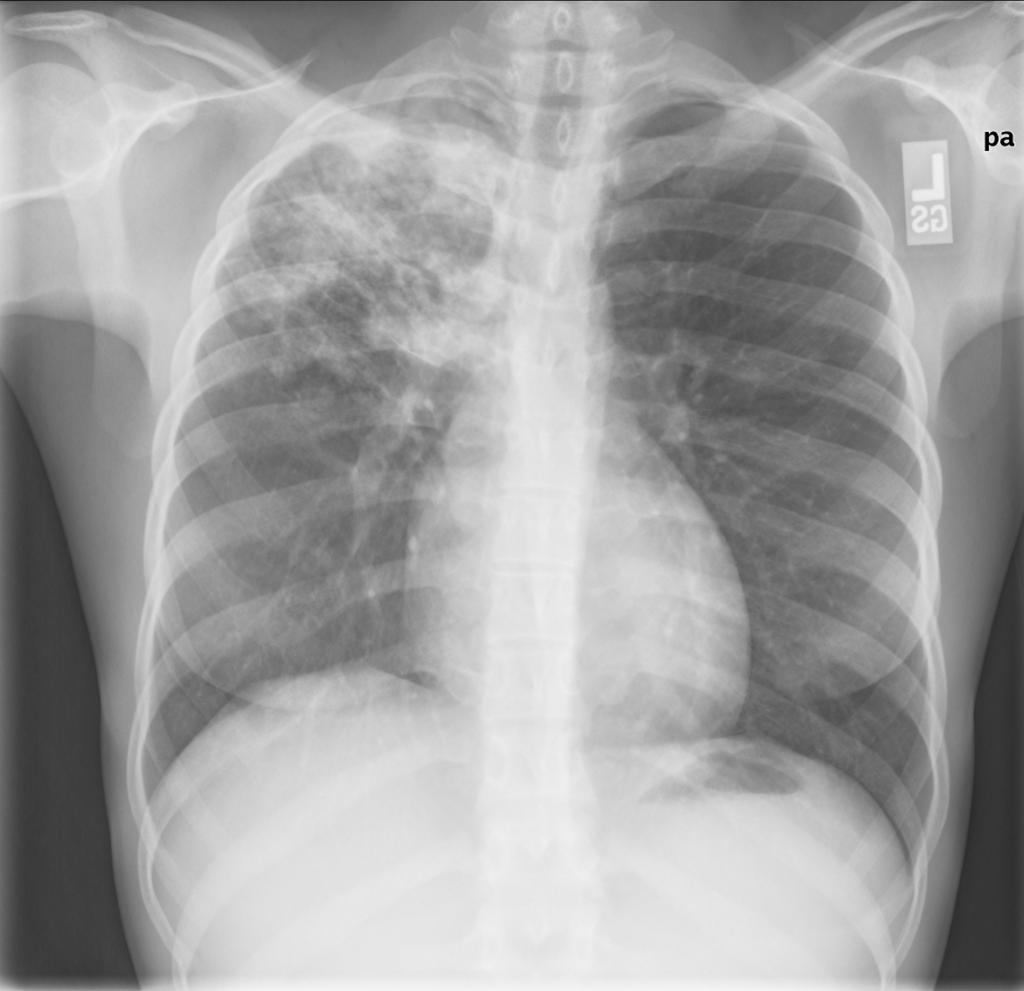

Describe the radiological appearances of TB